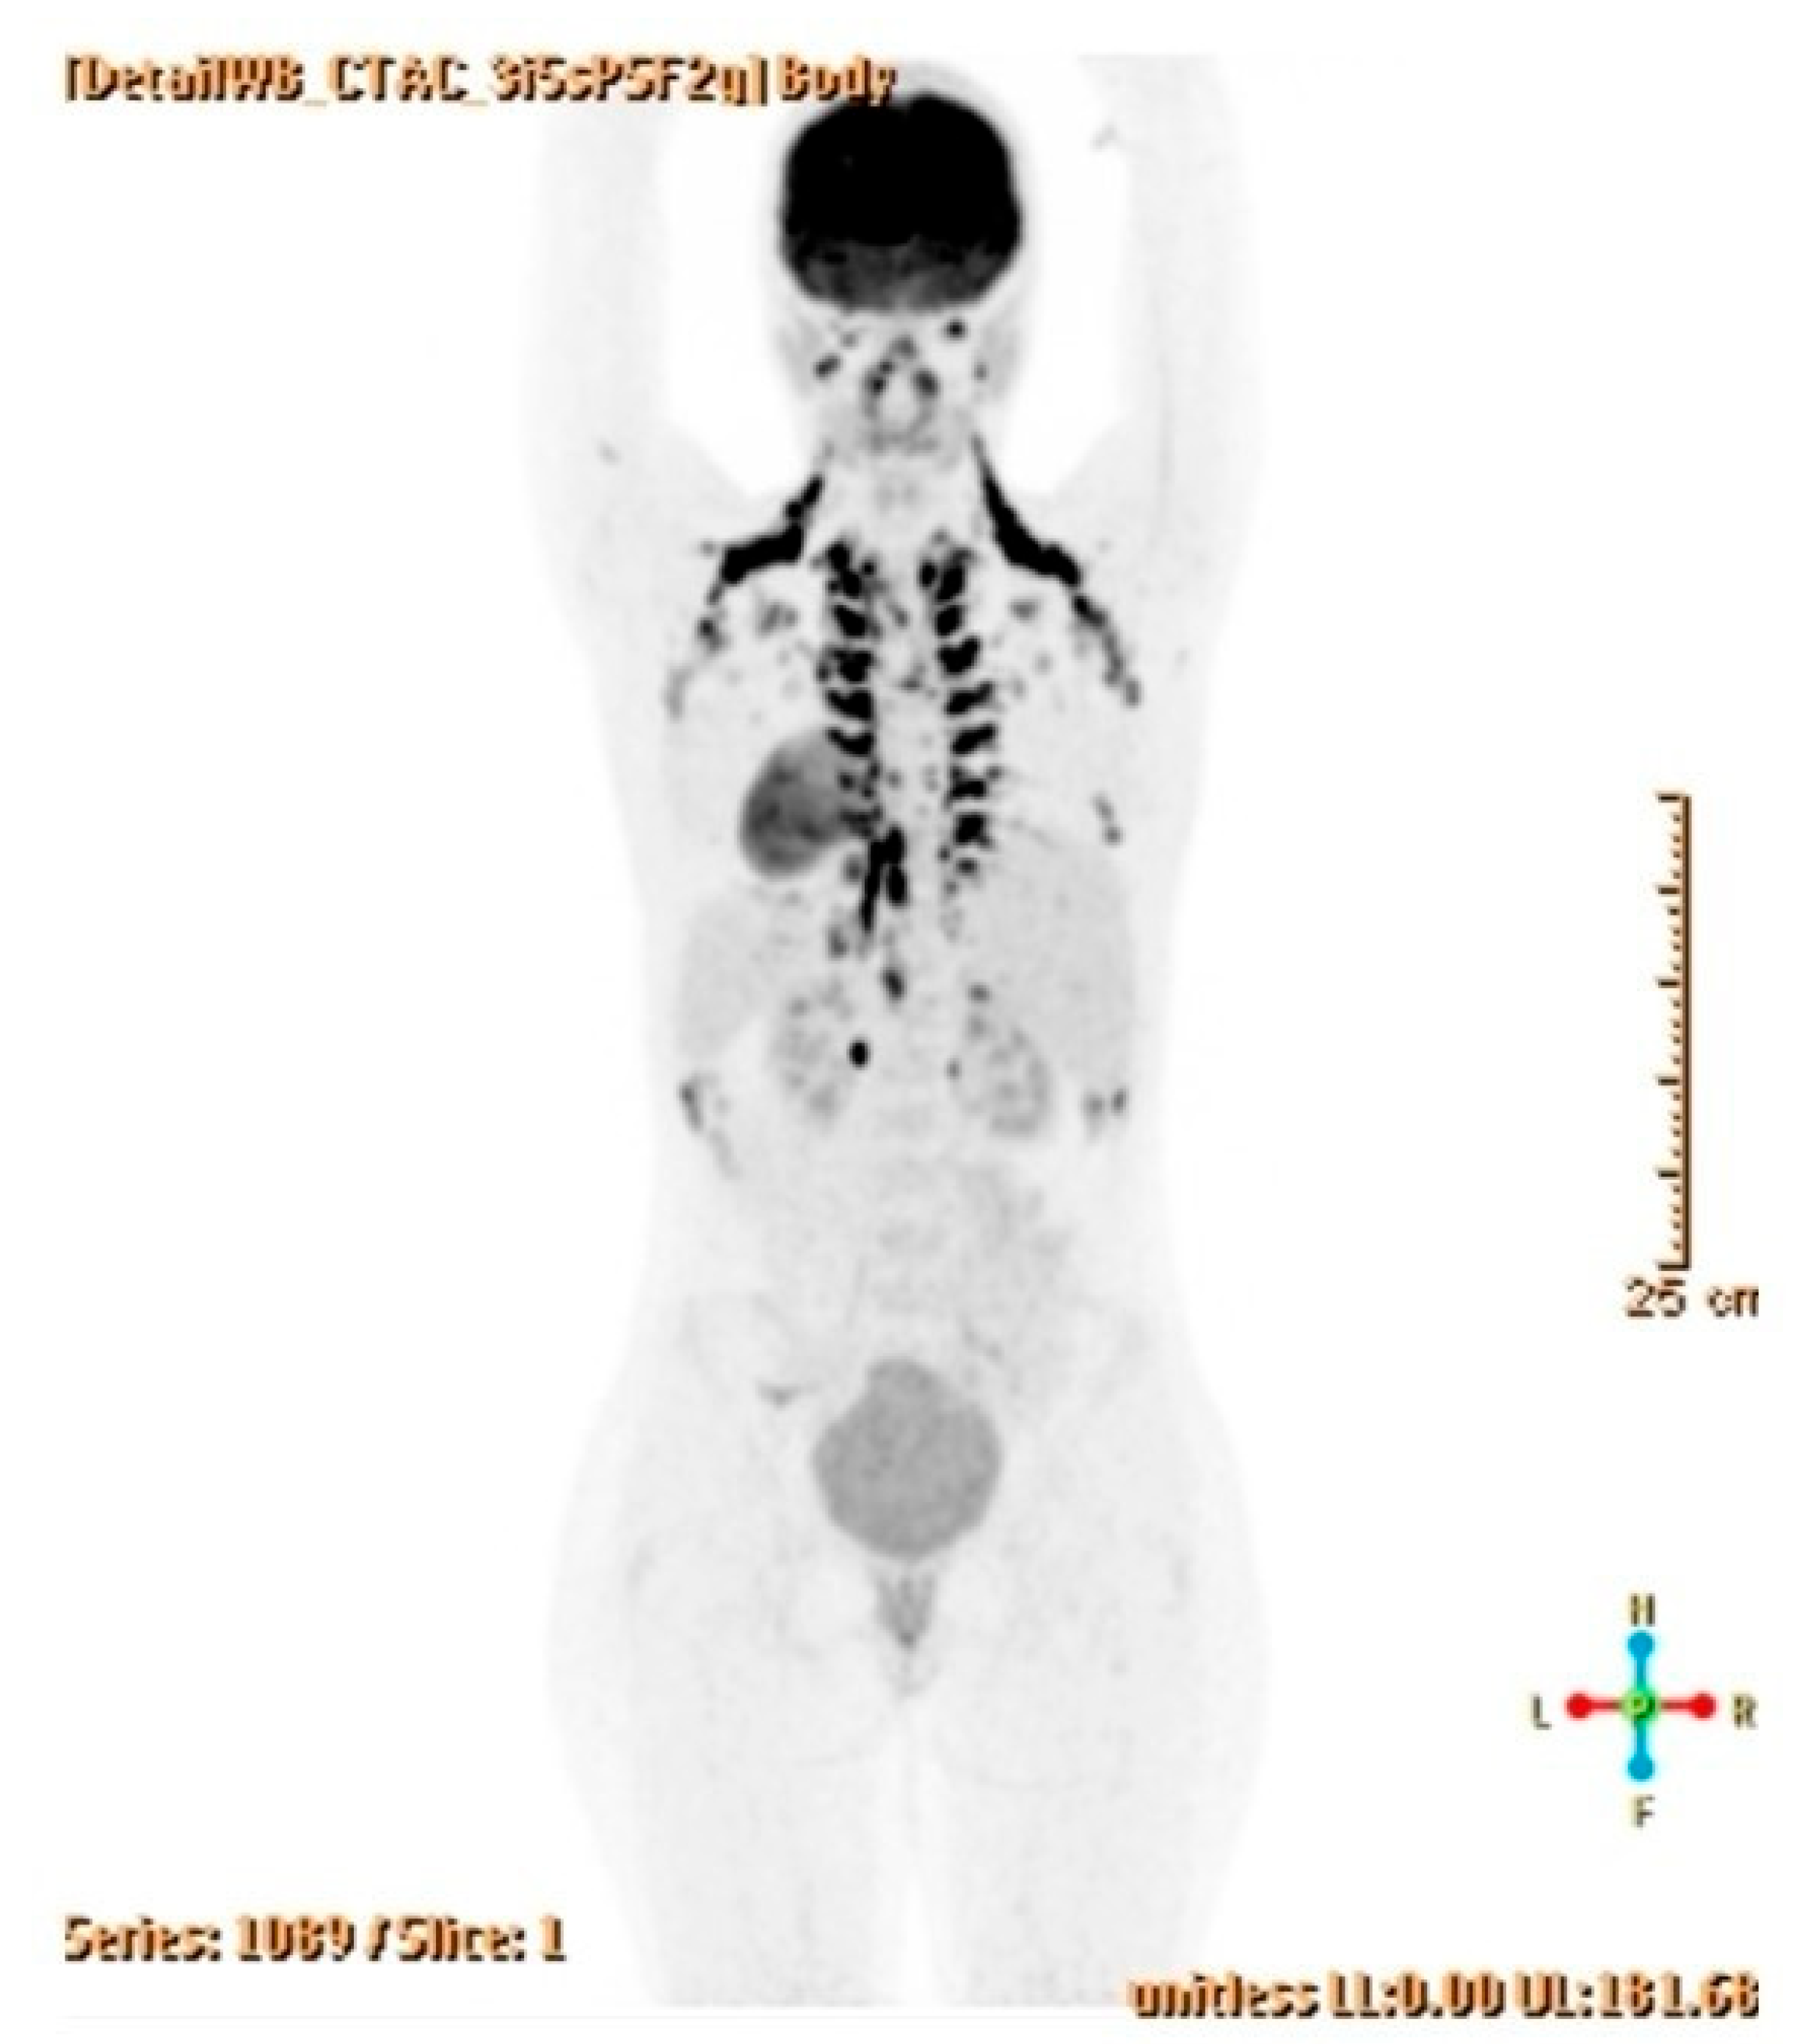

2.3. Diagnostic Assessment